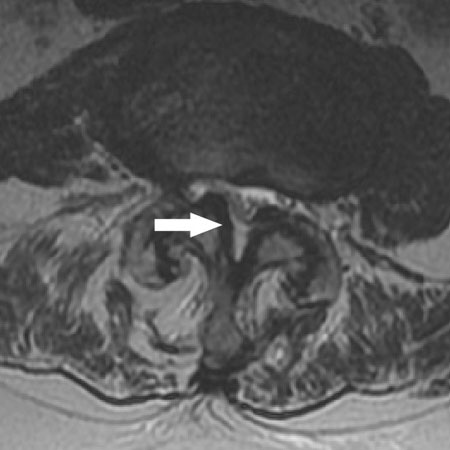

Magnetic resonance imaging of spinal stenosis: arrow points to the moderately stenotic spinal canal caused by hypertrophic facets and ligament flavum

Axial view of a vertebral body showing central spinal stenosis